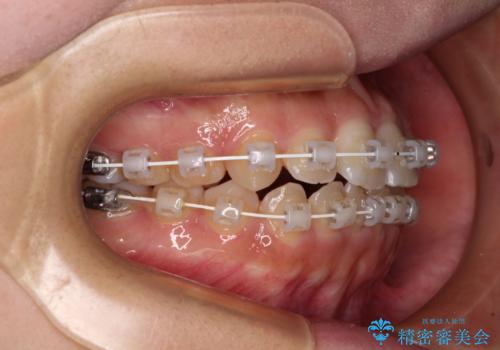

- 矯正装置

- 審美装置

- 前歯のデコボコを気にして来院された患者様です。

マウスピース矯正のような自己管理の煩わしさがなく、早く治療を終えたいとのことで、ワイヤー装置による矯正治療を行うこととしました。

当初予定通り、1年で治療を終えることができました。